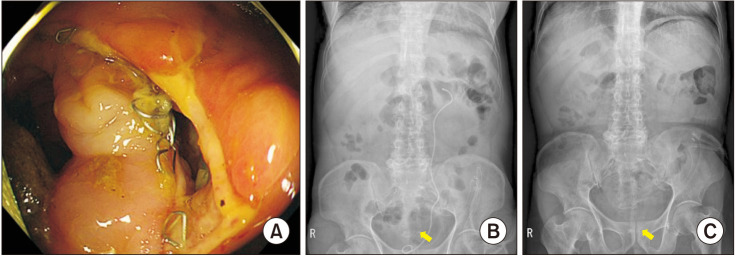

Abstract Image